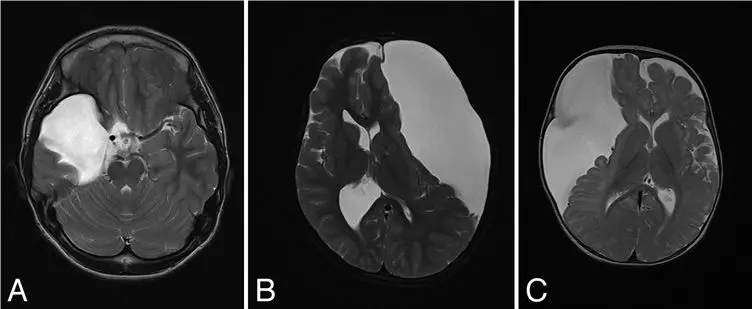

儿童起病的颅咽管瘤是源自鞍内和鞍旁的罕见胚胎源性肿瘤,尽管肿瘤组织学为WHO I级,患儿有较高的存活率(90-95%),但由于肿瘤压迫视神经和下丘脑-垂体轴引起的神经内分泌并发症,存活患儿的生活质量(QoL)严重受损;同时,儿童起病的颅咽管瘤具有更高的致死率,往往继发于脑血管事件死亡。因此,基于开颅手术治疗颅咽管瘤的经验,部分术者反对全切肿瘤(GTR)。来自日本东京的Shozo Yamada教授回顾性分析了1990年至2015年间由他主刀完成的65例(45例为首次手术,20例为再次手术)经蝶手术(TSS)颅咽管瘤的疗效,手术的目标是GTR。他的经蝶手术经历了以下术式演进:显微镜下TSS(唇下-蝶窦入路<10岁,鼻蝶入路>10岁)(2000年以前),内镜辅助下TSS(2000年-2012年),纯内镜下TSS(2012年后)。59例肿瘤(91%)获得GTR,首次手术组的GTR高于再次手术组;GTR后,12%的病例再次复发(平均随访时间7.8年,首次GTR组复发率低于再次GTR组)。首次手术组中,80%的患儿术后有垂体功能低下,83%出现尿崩(DI),而再次手术组全部患儿术后出现上述两种并发症。在57例术前没有肥胖的患儿中,9%的原发手术组和21%的再次手术组患儿术后出现肥胖,提示尽管积极切除肿瘤,下丘脑功能紊乱似乎与GTR关系不大。该研究结果初步认为TSS首次治疗儿童颅咽管瘤要力争全切,当肿瘤无法全切或全切后复发时,推荐行放疗。

经蝶手术治疗鞍内、鞍上、鞍膈上和脑室内型颅咽管瘤手术前后对比